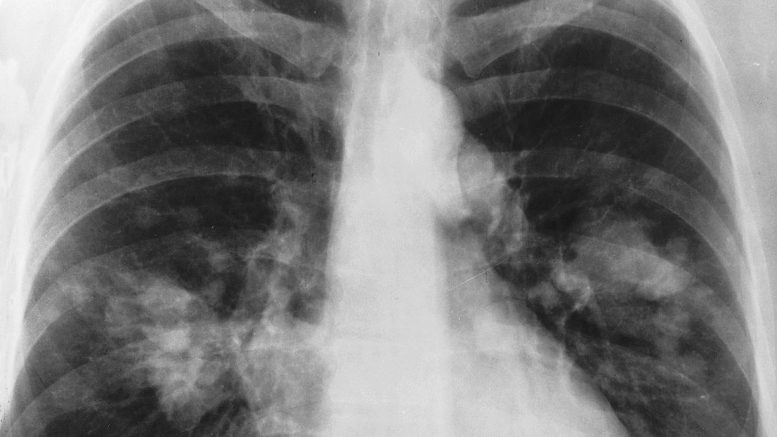

Il professore Lococo spiega che “Il nodulo polmonare è spesso l’espressione di una neoplasia allo stadio iniziale, pertanto più la diagnosi è precoce maggiori saranno le probabilità di guarigione. Cosa è cambiato oggi nella lotta al tumore del polmone? Al primo punto la prevenzione con la lotta al fumo, un più corretto stile di vita ma soprattutto i progressi nelle campagne di screening. Al secondo punto il ruolo delle linee guida con la stesura delle nuove linee guida nazionali a cura del PNR-Group. Al terzo punto la chirurgia mininvasiva, le moderne terapie biologiche e la più recente immunoterapia. Il tutto coordinato dai Gruppi Interdisciplinari del PDTA Oncologico”.